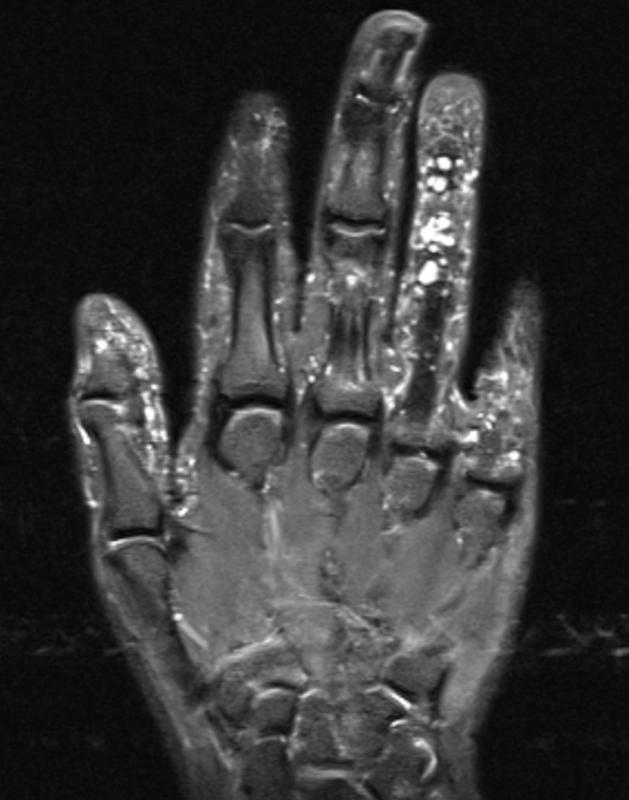

2212b132f57f8a60dd9c7f4a1305da10.jpgbe9dd1677b8ba2e94f3d512ce7329ad5.jpg

左手第4指的矢状位质子密度(PD)加权图像显示掌侧表皮下多个毫米级的结节状高信号强度病变(箭头),在T1加权图像上,这些结节表现为小的中等信号强度病变(箭头)。